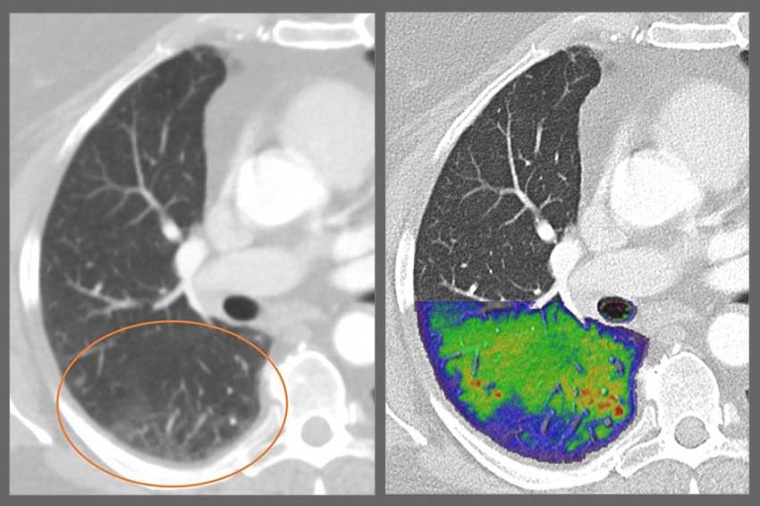

Thanks to the revolutionary images provided by photon-counting CTs, more people all over the world will benefit from precise and comprehensive examinations at low radiation and contrast dose – from oncological procedures and heart diagnostics to lung follow-up checks for respiratory illnesses.

The centerpiece of this innovation is the new photon-counting detector whose active detection layer consists of a cadmium telluride one crystal (CdTe) and offers clear advantages over conventional CT detectors. Standard CT detectors convert the X-rays in a two-step process first into visible light that is subsequently detected by a light sensor, ultimately producing the final image. Due to this intermediate step, important information about the energy of the X-rays is lost and no longer available to aid in diagnosis; contrast is reduced, and images lack clarity.

The photon-counting CT detector developed by Siemens Healthineers no longer converts the X-rays into visible light. The X-ray photons are converted directly into completely digital electrical signals and then counted without information loss. This adds a wealth of completely new clinically relevant information and improves image sharpness and contrast.